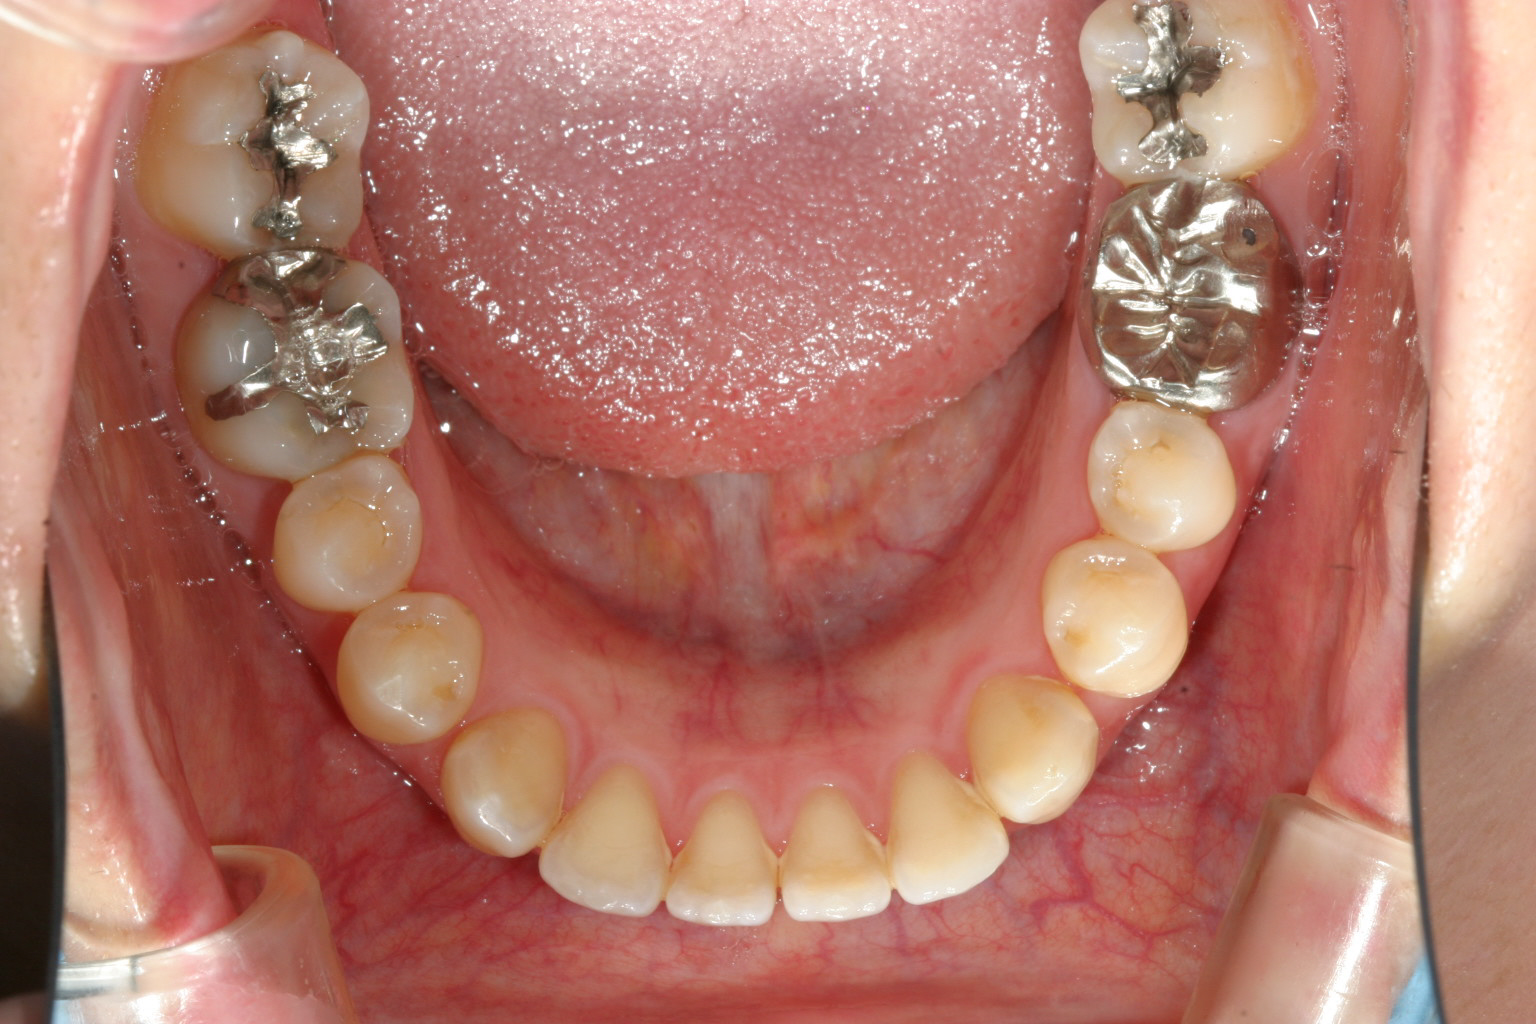

下顎もあちこちすきっ歯が目立ちます。

下顎も全体的に締め付けました。